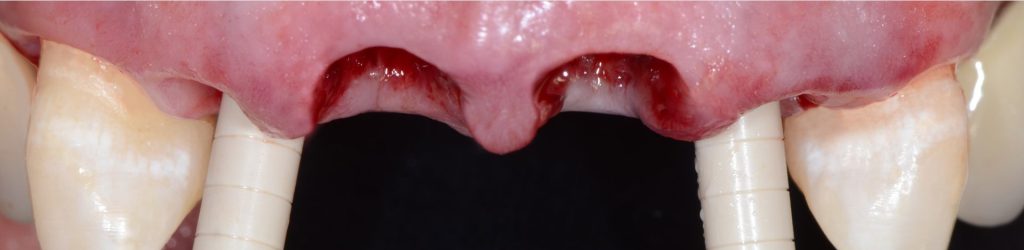

בסמוך למרפאתנו הקמנו חדר הרצאות חדשני וייחודי. ייעודו של האגף החדש הינו להגשים חלום יקר לליבנו, לממש ולקיים מרכז להכשרה קלינית לרופאים ובהדרכה אישית: A PRIVATE ACADEMY. במרכז יתקיימו הרצאות, קורסים עיוניים ומעשיים בהם תהיה צפייה בניתוחים בשידור חי, מחדר הניתוח בזכות מיטב הטכנולוגיה החדשנית. במתחם החדש, אנו נארגן מגוון רב של פעילויות, ומאמינים כי ביכולתנו לתרום מניסיוננו לטובת ציבור רופאי השיניים הכלליים. הקורסים מיועדים לכלל ציבור רופאי השיניים המעוניינים להעשיר את בסיס הידע ואת יכולתם הקלינית בתחומים שונים (פריודונטיה, אימפלנטולוגיה ואסתטיקה), דבר שישרת אותם במרפאתם. המרצים יהיו רופאי המרפאה יחד עם רופאים בכירים ומומחים נוספים אשר יצטרפו לצוות.